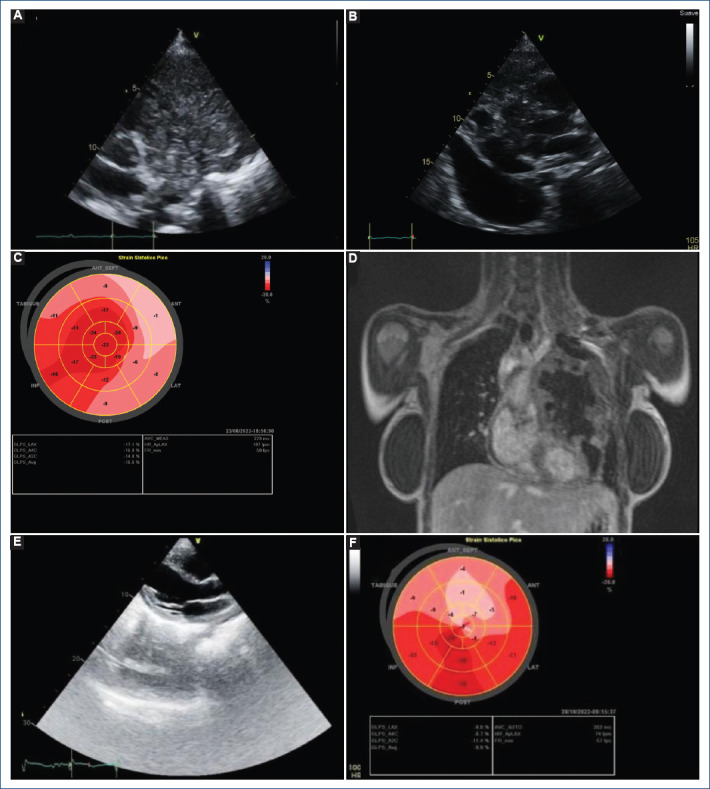

A disastrous dyad: fibrinous pericarditis and cancer therapy-related cardiac dysfunction in primary mediastinal diffuse large B cell lymphoma.

Andrea Nájera-Rojas, Ximena Latapi-Ruiz-Esparza, Rodrigo Gopar-Nieto, Diego Araiza-Garaygordobil, Daniel Sierra-Lara-Martínez